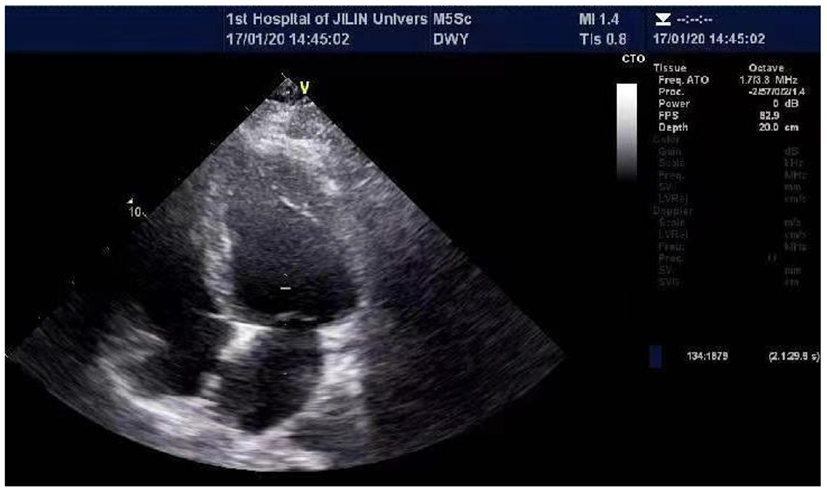

He was admitted to the hospital with a high fever and numerous joint pains throughout his body for 4 days, with a temperature of up to 39°C in January 2020. At admission, his body temperature was 36.8°C, his heart rate was 84 beats per min, his blood pressure was 126/69 mmHg, and he was unable to walk upright. He is 175 cm tall and weighs 97 kg. His BMI is 31.67 kg/m2, which is overweight. Laboratory findings are as followed: CK 514U/L, CRP 43.41 mg/L, Interleukin-4 (IL-4) 3.42 pg/ml, IL-6 10.17 pg/ml, IL-10 8.13 pg/ml, tumor necrosis factor-α(TNF-α) 3.16 pg/ml. CT scan of the lungs revealed a small amount of inflammation in the left lower lobe and in the right lower lobe. After anti-infection treatment, he was discharged. After half a year, he was hospitalized again for a fever and muscle pain. Laboratory findings are as followed: CK 411 U/L, CK-MB 7.40 ng/ml, troponin I (Tn I) 0.067 ng/ml, N-terminal pro-B type natriuretic peptide (NT-pro BNP) 1250.0 pg/ml, CRP 45.67 mg/L, LDH 257U/L, mycoplasma antibody: positive. The lung CT was similar to the last one. In the abdominal CT, it was found that the patient had fatty liver, multiple enlarged lymph nodes around the abdominal aorta, and less muscle density on both sides of his back and buttocks, which should consider the possibility of fat infiltration. During echocardiography (Figure 1), the left ventricular ejection fraction (EF) was 39%, and left ventricle were enlarged (left ventricle endomesosomal diameter was 63 mm), abnormal ventricular movement, decreased left ventricular systolic and diastolic function, weak mitral regurgitation and trace pericardial effusion. The ECG showed sinus rhythm, a normal ECG. This time his cardiac function was level III and was placed on hormone therapy. He was discharged when his condition improved.

Figure 1

Echocardiographic of the patient's heart. The echocardiography revealed EF 29%, left atrial and left ventricle enlargement (left ventricular endomesosomal diameter 63 mm), reduced ventricular wall pulsation diffusion, decreased left ventricular systolic and diastolic function, and trace pericardial effusion.